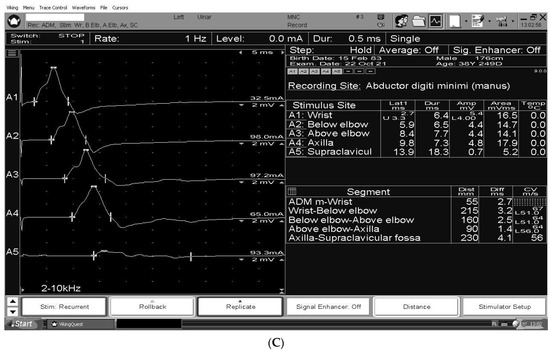

3. The Electrodiagnosis